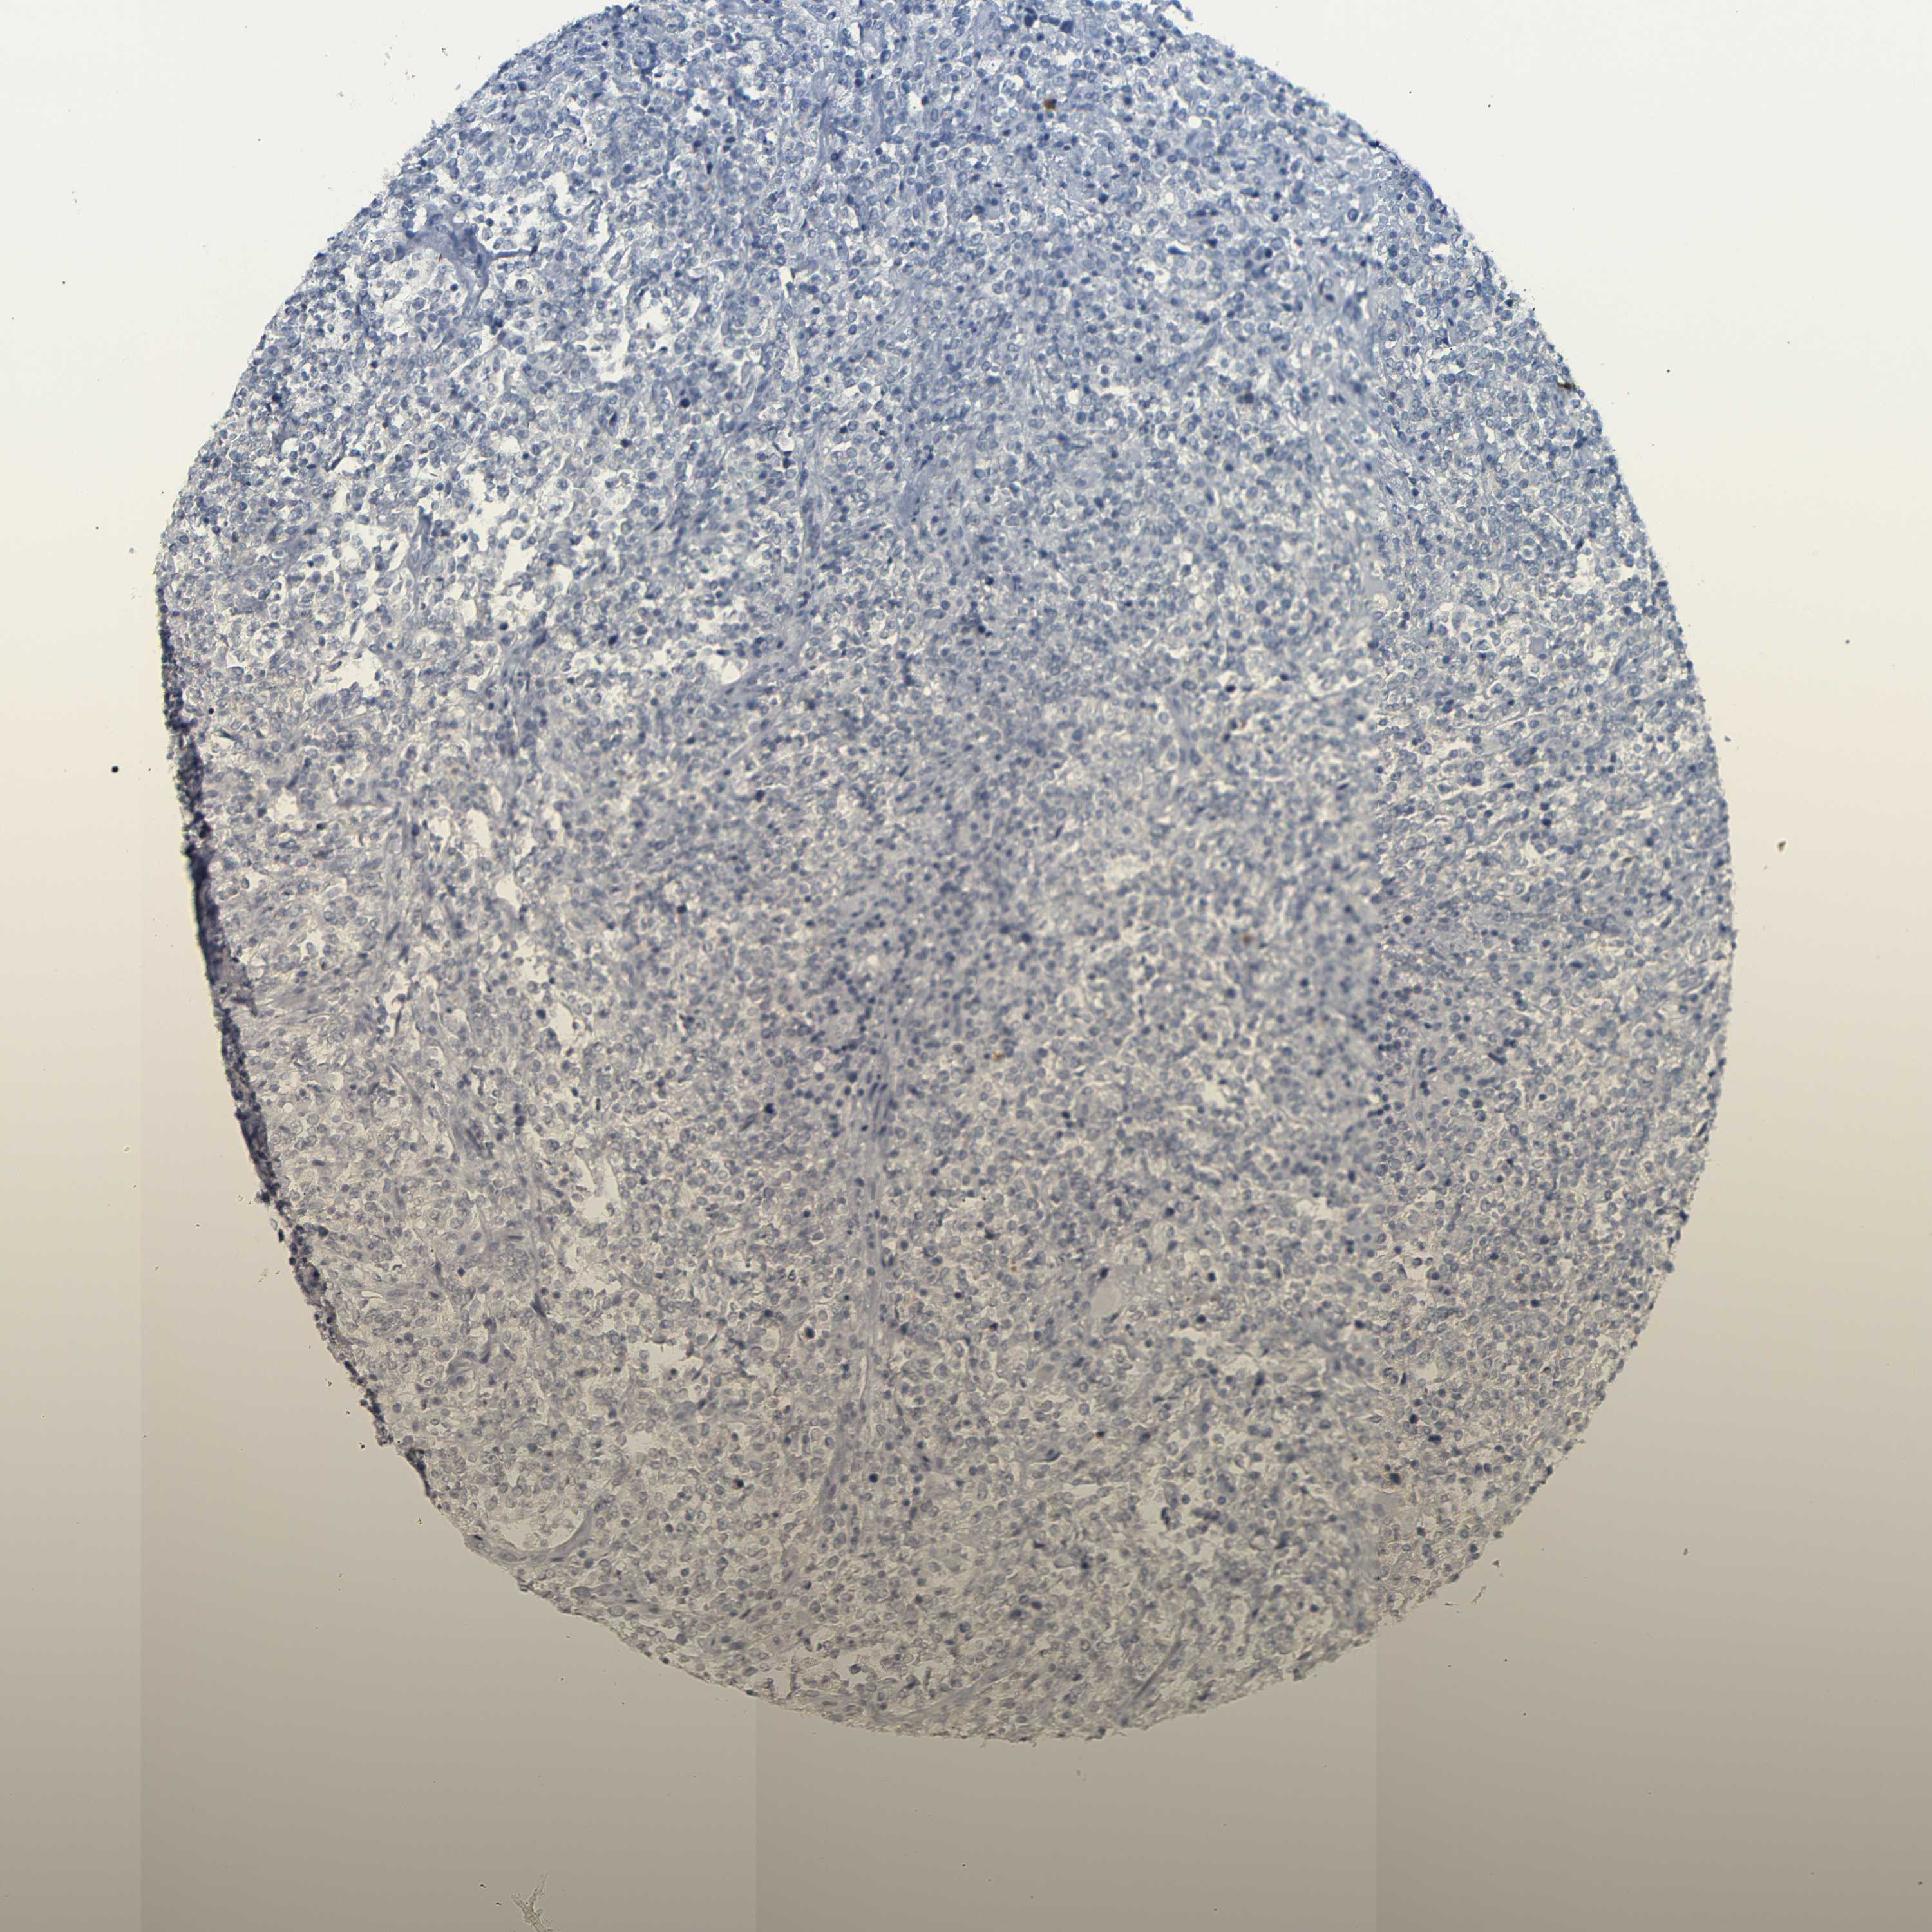

LYMPHOMA - Protein expressioni

A mouse-over function shows sample information and annotation data. Click on an image to view it in a full screen mode. Samples can be filtered based on level of antibody staining by selecting one or several of the following categories: high, medium, low and not detected. The assay and annotation is described here.

Antibody stainingi

Antibody staining in the annotated cell types in the current human tissue is reported as not detected, low, medium, or high, based on conventional immunohistochemistry profiling in selected tissues. This score is based on the combination of the staining intensity and fraction of stained cells.

Each image is clickable and will lead to virtual microscopy that enables deeper exploration of all samples and also displays staining intensity scores, fraction scores and subcellular localization as well as patient and tissue information for each sample.

Antibody HPA013323

Hodgkin's disease, NOS

Malignant lymphoma, non-Hodgkin's type, High grade

Malignant lymphoma, non-Hodgkin's type, Low grade